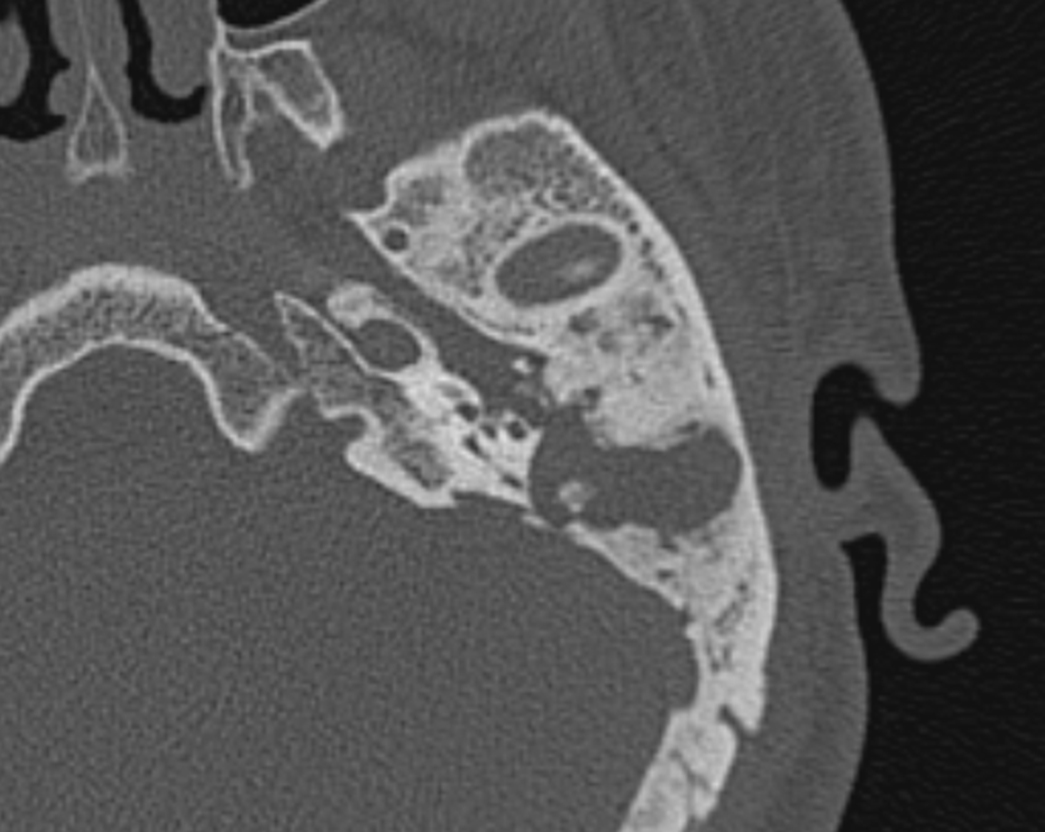

Пациент с эпитимпанитом, у которого в анамнезе была проведена антромастоидотомия на имплантируемом ухе. КИ проводилась одномоментно с ревизией мастоидальной полости. В ходе операции при отсепаровке мягких тканей в антромастоидальной полости визуализировалась холестеатома (рисунки 1, 2).

Рисунок 1. КТ левой височной кости пациента до проведения оперативного вмешательства. Послеоперационная полость после антромастоидотомии тотально заполнена холестеатомными массами, наличие фистулы лабиринта, обнажение барабанного сегмента лицевого нерва.

Figure 1. CT of the left temporal bone of the patient before surgical intervention. The postoperative cavity after antromastoidotomy is totally filled with cholesteatomic masses, the labyrinth fistula is present, the tympanic segment of the facial nerve is exposed.